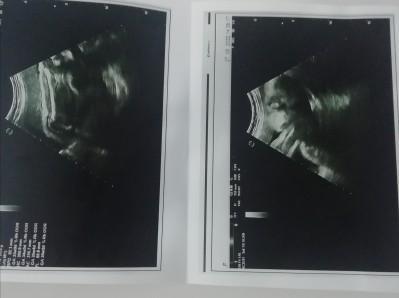

Arkadaş lar bakın bu benm bebişim herhangi bir anormallik görünüyor mu burdan bakınca

Gebelik haftası 36+4

Kafası küçük 1 hafta geriden gidiyo dedi canım

Kafası küçük 1 hafta geriden demişti canm